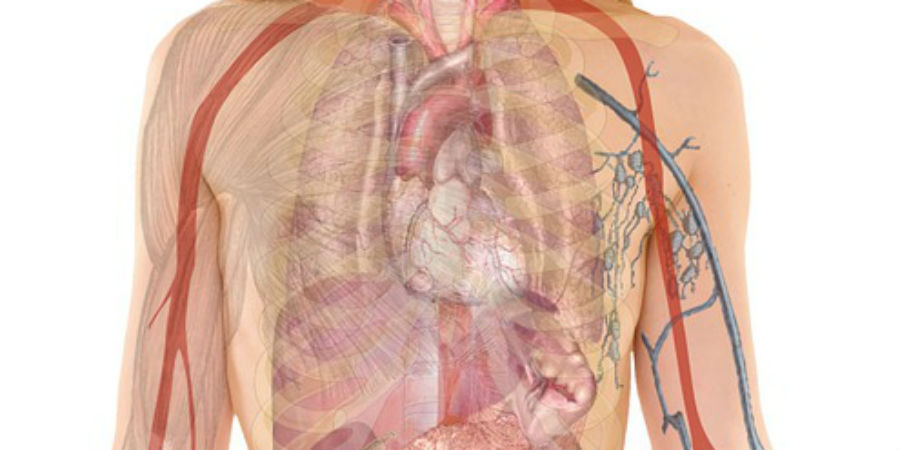

Een afbeelding van het interstitium onder de bovenste huidlaag. Volgens de onderzoekers is het orgaan een lichaamsbreed netwerk van met elkaar verbonden, met vloeistof gevulde ruimtes, ondersteund door een netwerk van sterke, flexibele eiwitten.